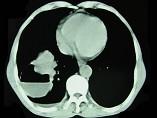

问题 男,76岁,胸痛伴咳嗽,咯血低热1个月,CT检查如图,最可能的诊断为 ( )

选项 A.右下肺脓肿 B.右下肺癌伴空洞形成 C.右下肺囊肿 D.右下肺包虫病 E.右侧包裹性积液

答案 B